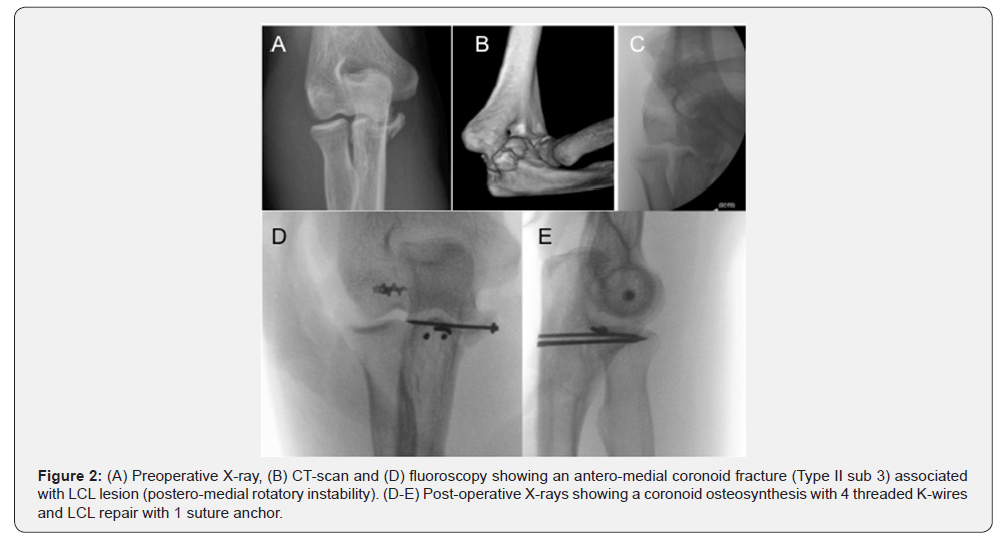

A number of techniques for coronoid fixation have been described, including transosseous sutures, K-wires, finethreaded K-wires, screws and mini-plates. However, the optimal treatment protocol and technique have yet to be established. The technique preferred by the authors of this chapter consists in using fine-threaded K-wires (FFS-Orthofix) [54]. They are inserted through the posterior aspect of the ulna, which is directed toward the coronoid using a one-step fixation technique. A varying number of fine-threaded K-wires of different diameters (1.2, 1.6, or 2.2 mm) can be positioned to increase primary and rotational stability depending on the num¬ber and size of the fragments. We have found that this technique provides easy, stable, mini¬mally-invasive and successful osteosyn¬thesis (Figure 2). When wide medial exposure is required or in comminuted fractures, osteosynthesis with precontoured miniplates is a valid alternative that increases the stability of the reconstruction and neutralizes biomechanical stress during early joint mobilization.

In their biomechanical study on postero-medial instability, Pollock et al. [55] recommended that small fragments (type IIsubtype 1) be treated by means of LCL repair alone, whereas larger fragments (type II-subtype 2 and type II-subtype 3) require fixation of the fracture fragment besides LCL repair. Park et al. [56] came to the same conclusion in their clinical study, adding that if the elbow remains unstable following coronoid fixation and LCL repair, the surgeon should investigate a hidden MCL injury, especially in subtype 2 fractures.

Hence, restoration of the LCL is of greater importance than bone fixation in type II-subtype 1 fractures because this injury may be associated with posterior dislocation. In type II-subtypes 2-3, anatomical reduction and fixation of the AMF and LCL repair are warranted because they act as a bone buttress that not only resists the varus force but also provides joint congruency [55,56]. When significant instability and/or unstable ORIF of the coronoid process persist, a HEF should be considered [23].